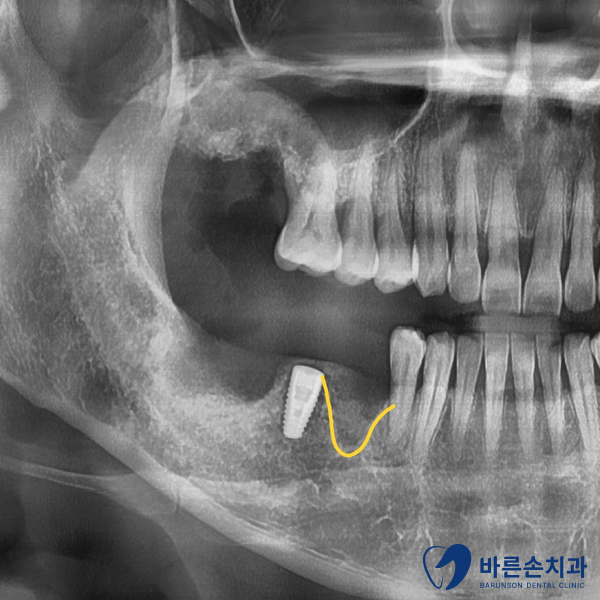

뒤에 임플란트(스트라우만 임플란트)를 식립함과

동시에 앞에 뼈이식을 해뒀습니다.

3달 후

이렇게 뼈가 단단하게 만들어져 하얗게 보입니다.